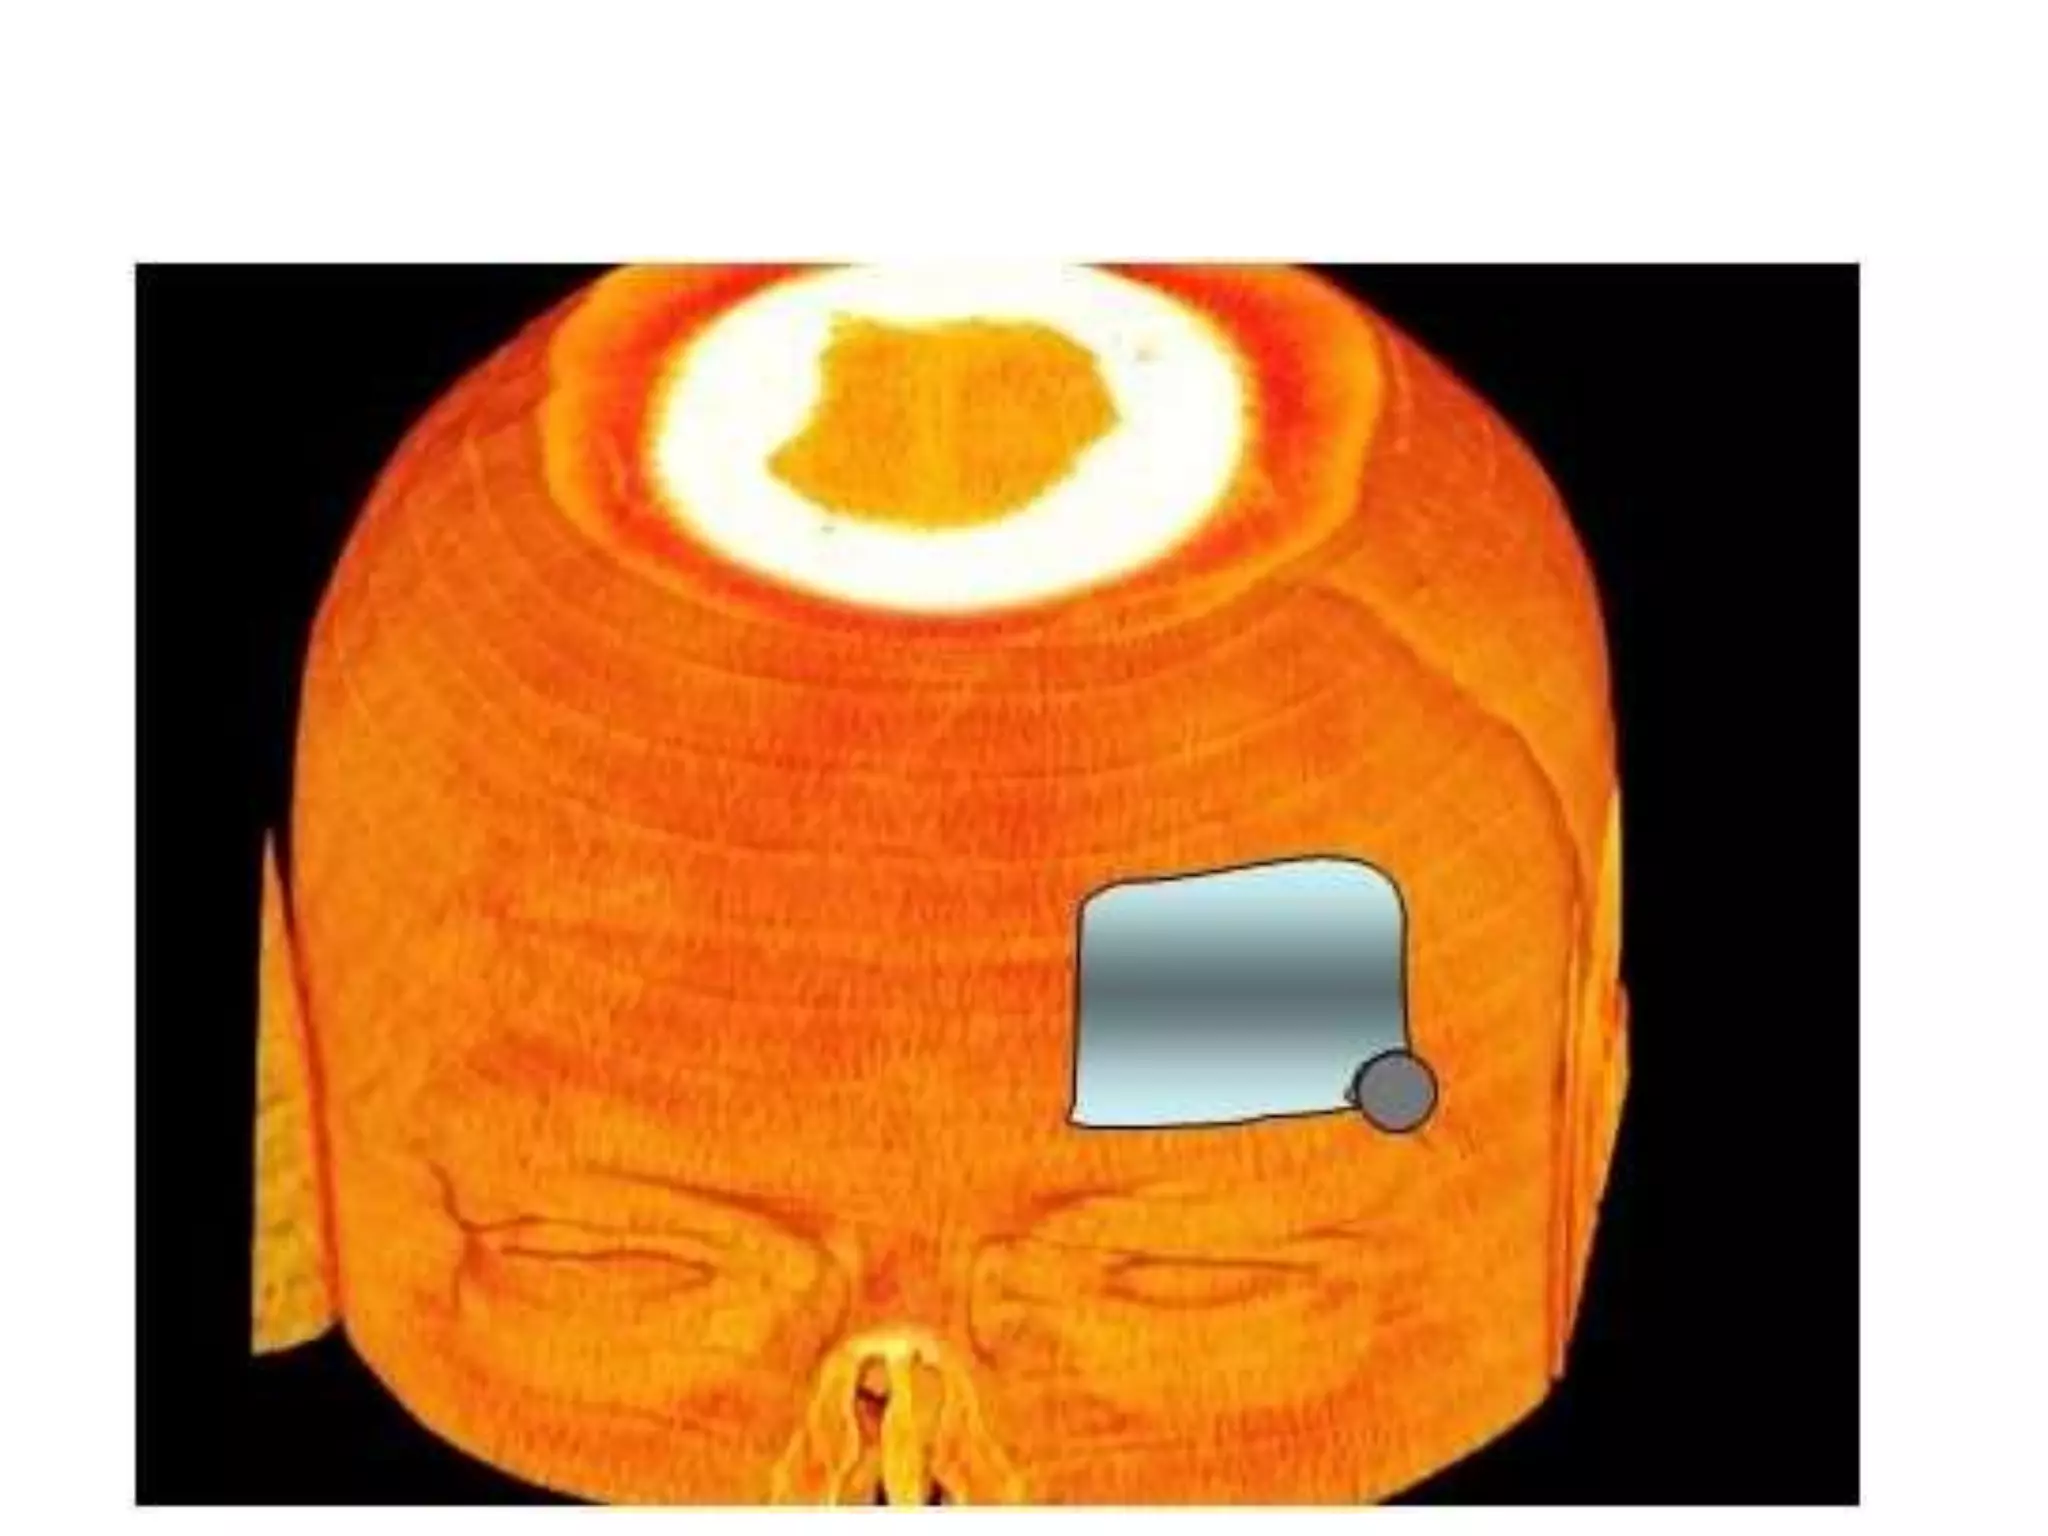

• Infratemporal approaches

• Approach that exposes the inferior aspect of

the temporal bone, with the jugular foramen

and the adjacent area of the parapharyngeal

space including the jugulo-carotid vessels .

• A large retroauricular and upper neck incision

opens the entry area. The dissection of the upper

neck exposes the jugular vein and carotid artery.

Removal of the outer ear canal and anterior

transposition of the VII cranial nerve allow drill

out removal of the infralabyrinthine petrous bone

up to the entire jugular foramen, to the occipital

condyle and low clivus.

• This typical skull base approach allows removal

of lesions from the CPA to the jugular foramen

and parapharyngeal space.